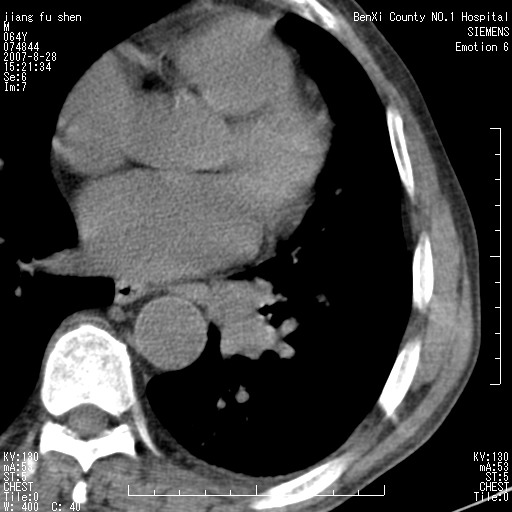

男、64、咳嗽、发烧一周、左肺呼吸音稍弱。既往肺结核,右手结核。

本次扫描患者未带原片,左肺下叶发现病灶。左肺上叶空洞,5组淋巴结肿大,1cm左右。

平扫20-33hu

增强31-33hu

1分半44-52

2分55-67

左肺下叶前内基底段支气管明显偏心性狭窄,周围分叶状肿块,伴有阻塞性肺炎,支持肺癌可能性大。

考虑左肺中央型肺癌并阻塞性肺炎

病灶边缘可见多量较长棘影及纤维条索状影,除外病灶边缘较光整,病灶有分叶表现,但多表现为较浅分叶,且向周围伸出之叶多呈尖角改变,且边缘较光整,病灶增强呈中度延时增强,且早期及中期仅轻度增强,结合患者病史,多考虑继发型肺结核,炎性增殖灶形成,不除外肺癌